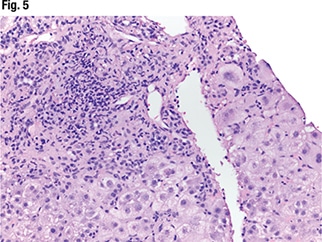

Under higher power (Fig. 3), interface hepatitis—in which inflammation enters the lobules—can be seen, as can inflammation in the portal tracts. In Fig. 4 (center), “there’s some spillage of the inflammation in the lobules but it’s mainly staying in the portal tracts at this point.” Under higher power (Fig. 5), “there are tons of plasma cells,” and lymphocytes are seen in the hepatocytes. “It’s somewhat rosetting the hepatocytes” (mid-left, bottom). “So there’s inflammation in the portal tracts, it’s spilling out tons of plasma cells, and there’s a selection of them going into the lobules and encasing the hepatocytes.”